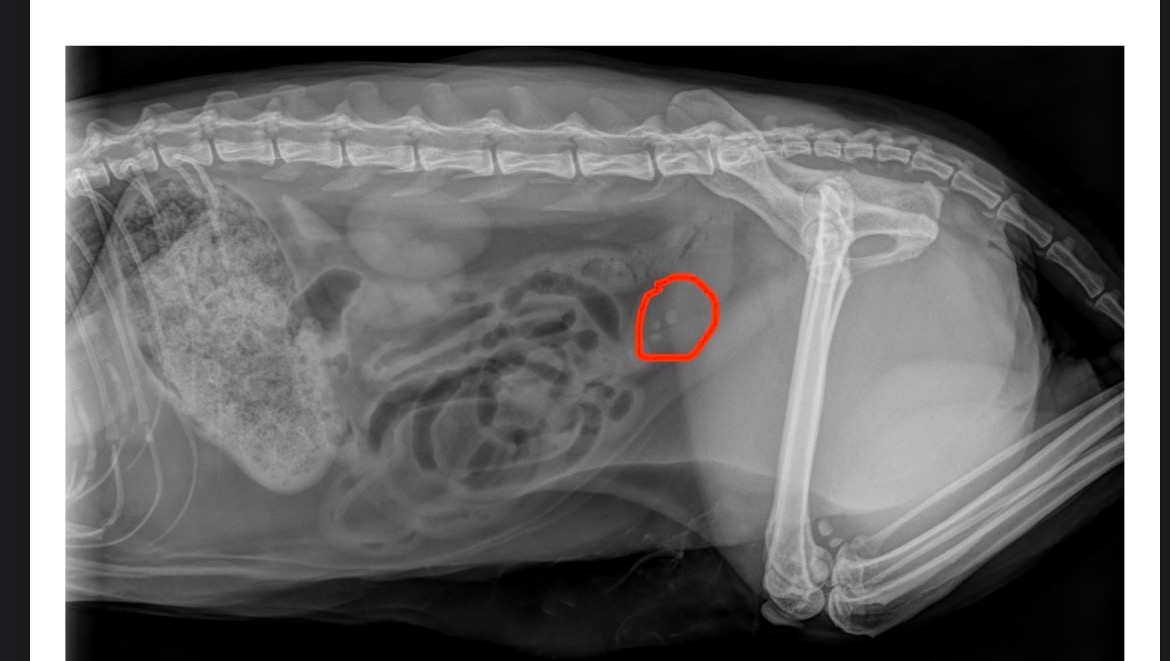

I took her to the vet for checkup fearing and hoping it wouldn’t be stones again and unfortunately the X-rays showed three stones in her bladder.

Knowing her previous symptoms 5 years ago, the size of the stones and due to the fact that she is already on specialized food, the vet says surgery again is the only way to make her comfortable again.

This will be her second surgery, and it pains me to see her going through this again. The stones present in her bladder are suspected to be oxalate crystals which are highly recurrent and not possible to dissolved through diet. She is also already on Royal Canin S/O urinary food but it seems to not be effective enough.